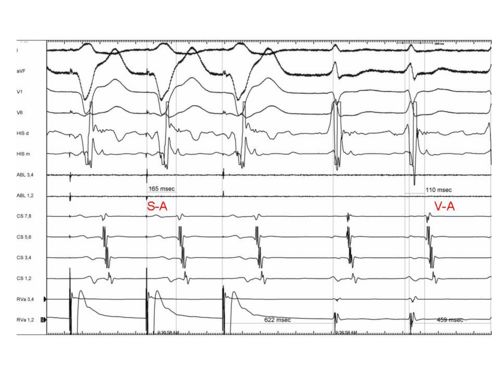

- Used to differentiate Atypical AVNRT from Septal Bypass Tract

- Measure Stimulus at onset of QRS on RV pacing channel to stimulus to A signal at HRA

- Calculate SA -VA interval

- SA - VA interval > 85 for Atypical AVNRT. (range 90 - 200)

- SA - VA interval < 85 for ORT using Septal Pathway (range 0-80)